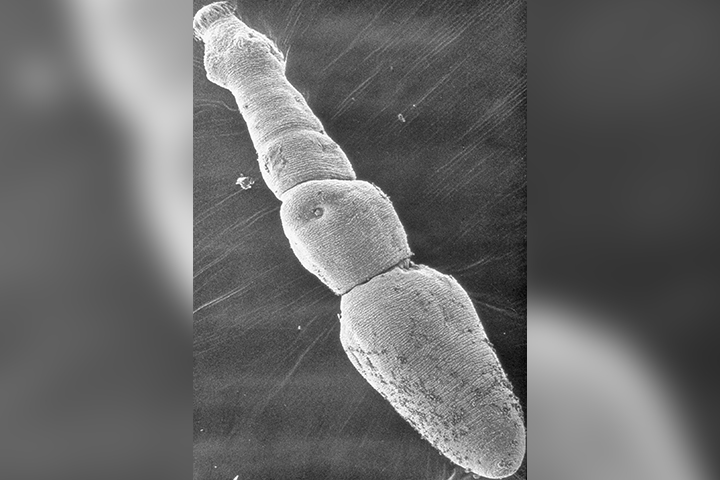

More cases of deadly tapeworm that causes tumour-like growths appearing in AlbertaThe tapeworm, which is often spread by coyotes, is increasingly infecting humans too.HealthJul 24, 2019

-